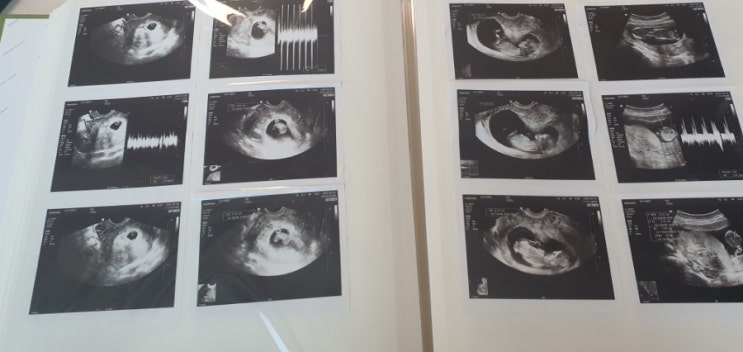

아기 초음파 사진 앨범에 넣기 17주 태동 일기

이롬이가 찾아온 뒤 12주 쯤 되었을 때 둥이들에게 이야기했어요. 가족 넷의 일상에 변화가 생기는거라 미...